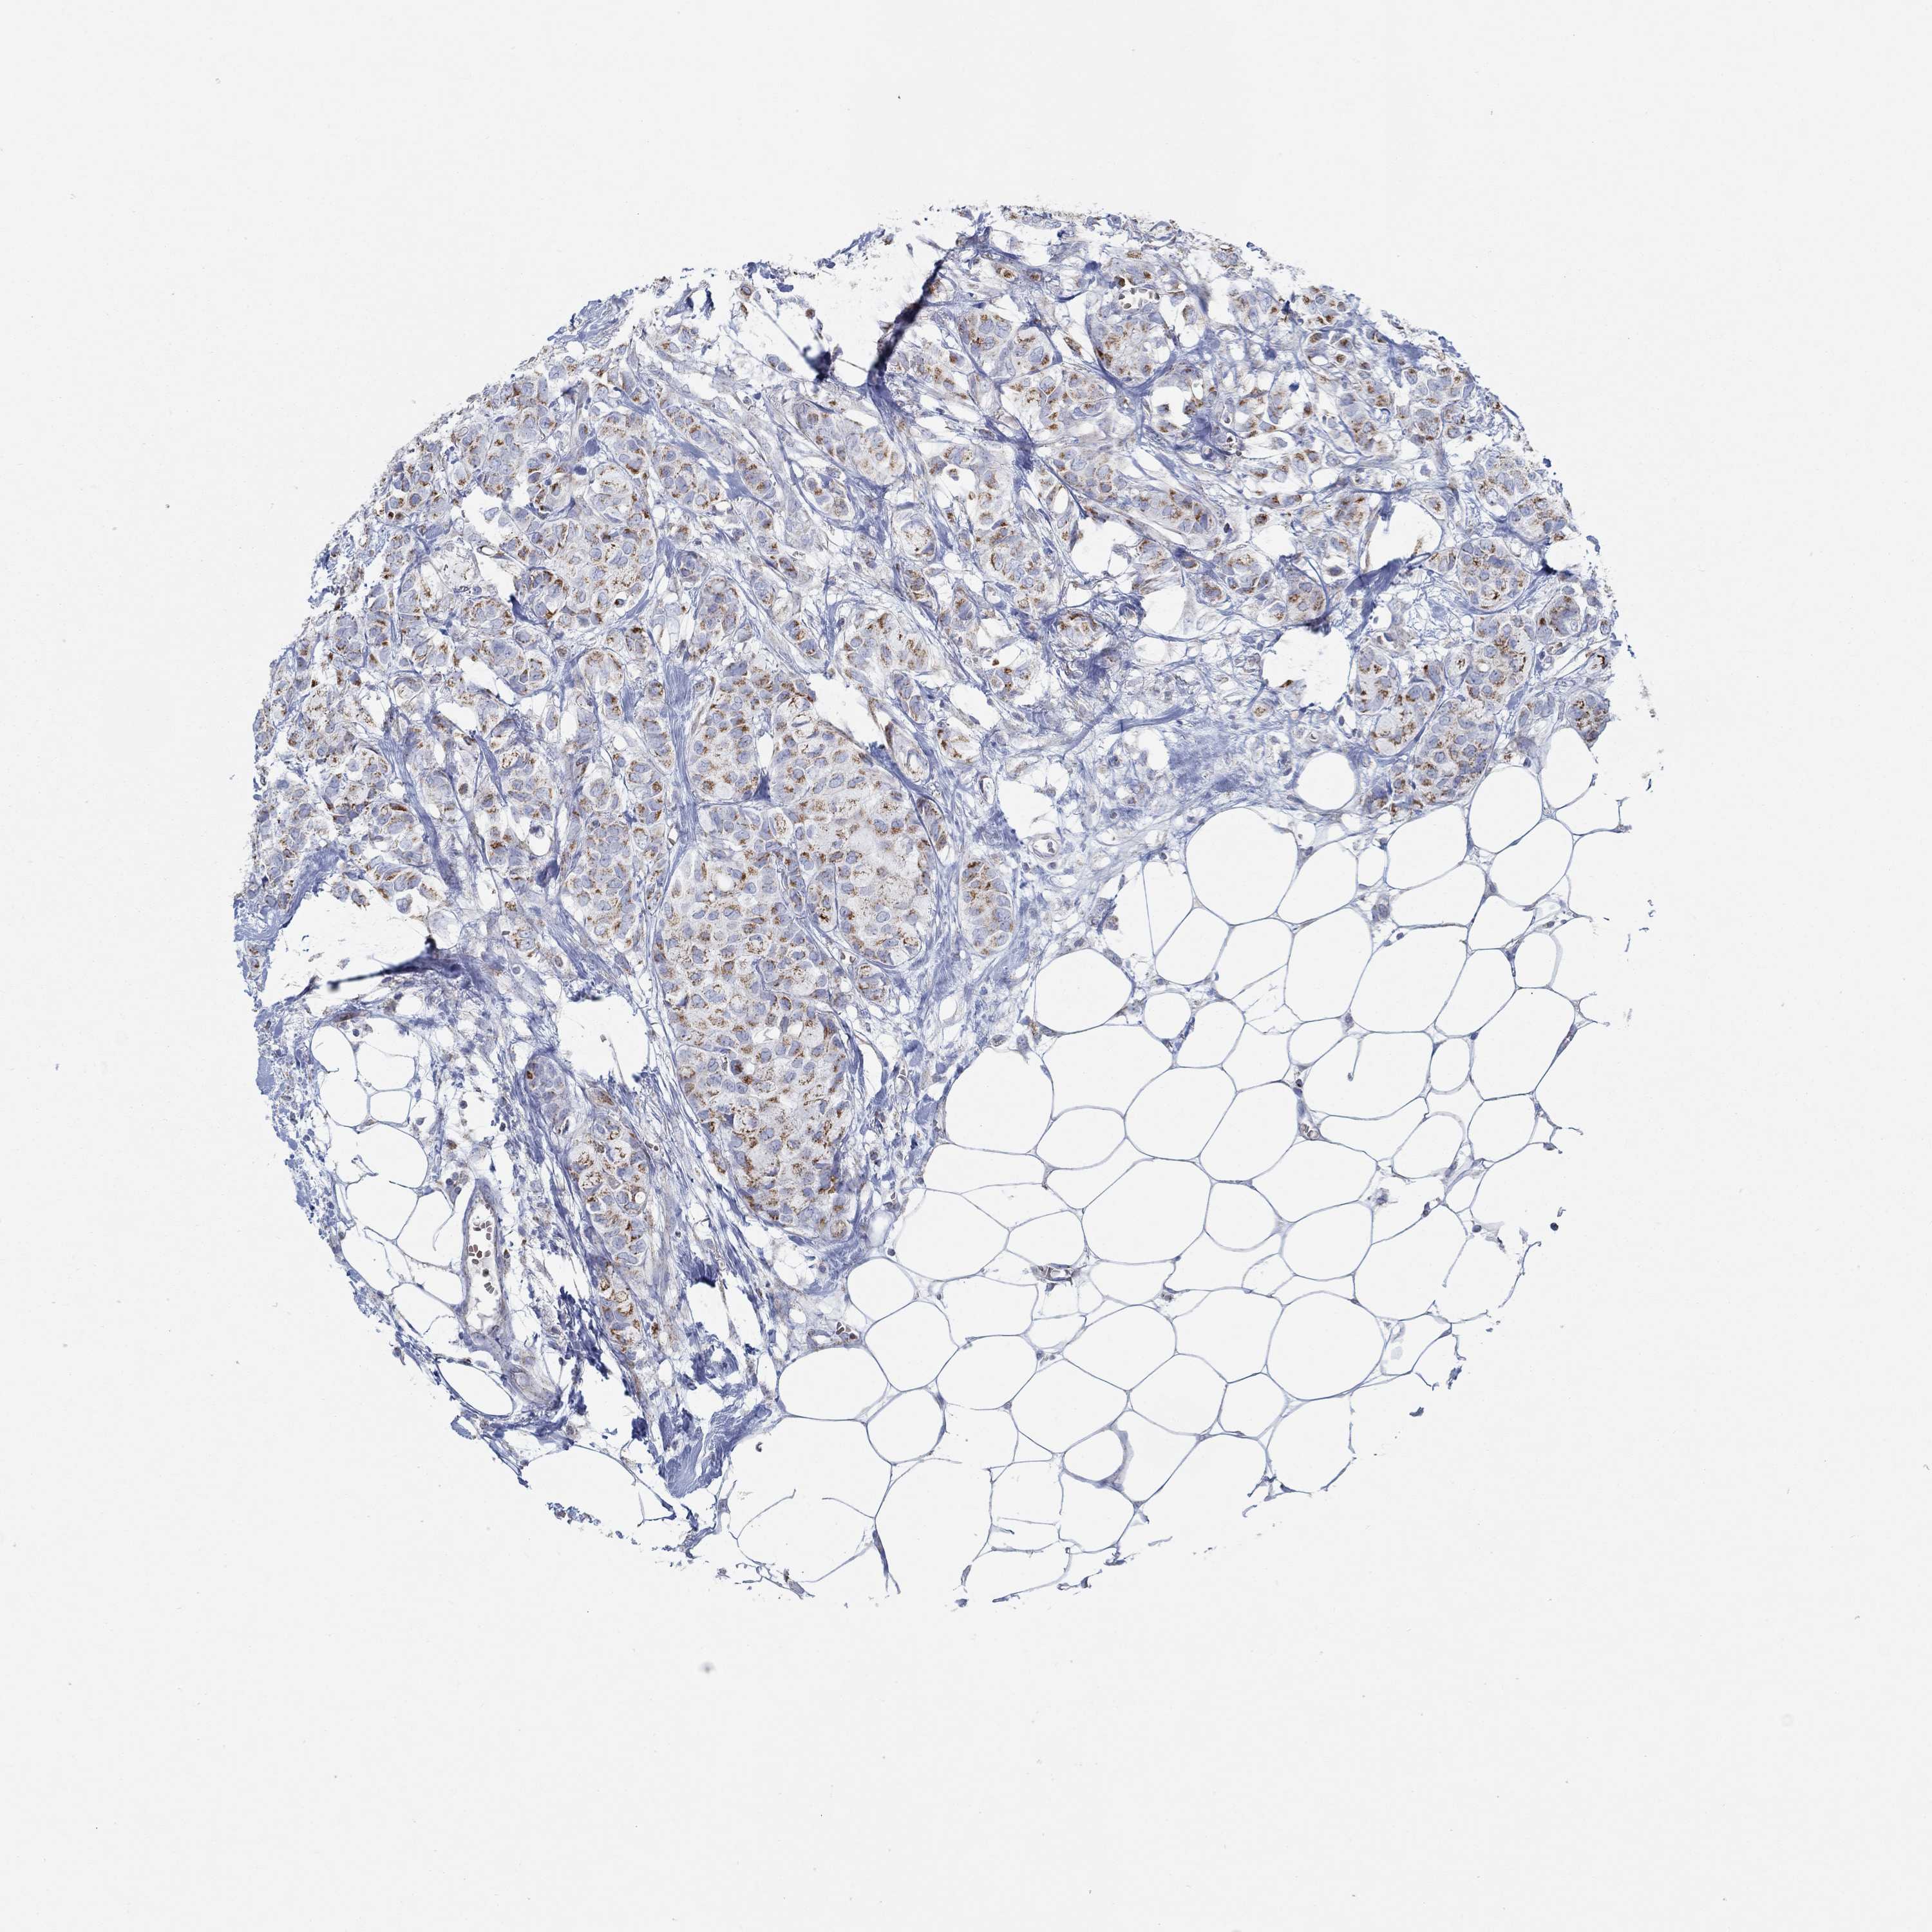

CANCER BREAST CANCER Show tissue menu

BRCA TCGA BRCA VALIDATION PROTEIN EXPRESSION

Breast cancer

Human cancer